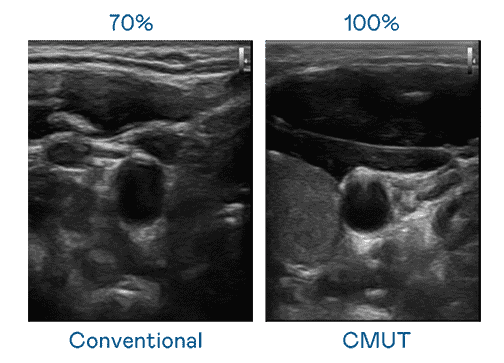

CMUT 技术是一种用电容式微机电元件来产生超音波讯号的技术。。。。与传统 PZT 压电式技术相比,,,,CMUT 频宽增加 30%,,,,更宽频的超音波讯号让影像解析度大幅提升,,,是实现高影像品质医疗超音波扫描、、、、促进精准医疗发展的关键技术。。。

大频宽带来超清晰影像

超音波影像的解析度高低,,,,首先取决于探头能发出的讯号频宽。。开云电子 CMUT 可提供高清晰的超音波讯号,,,提供高频宽、、、、高灵敏度、、影像纹理细节更高的超音波影像,,协助医护人员缩短影像判读时间及利用精准的医疗影像进行诊断。。。